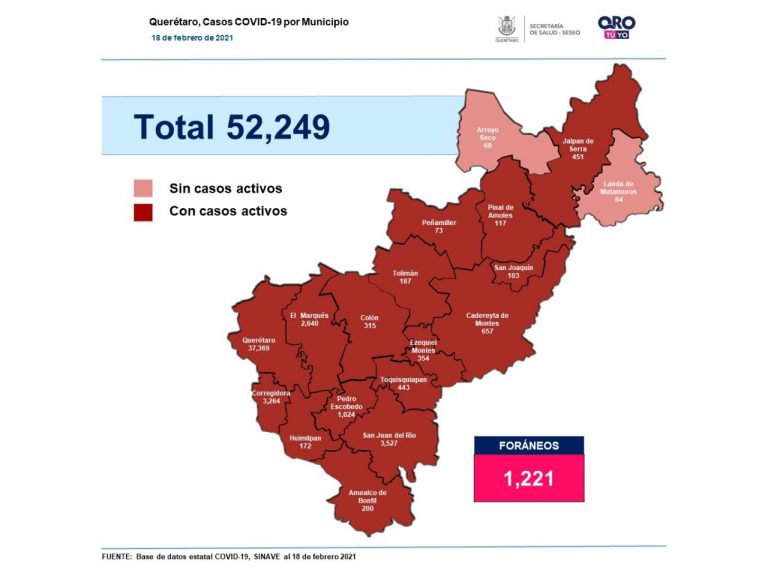

Se suman 227 casos de Covid-19 en Querétaro